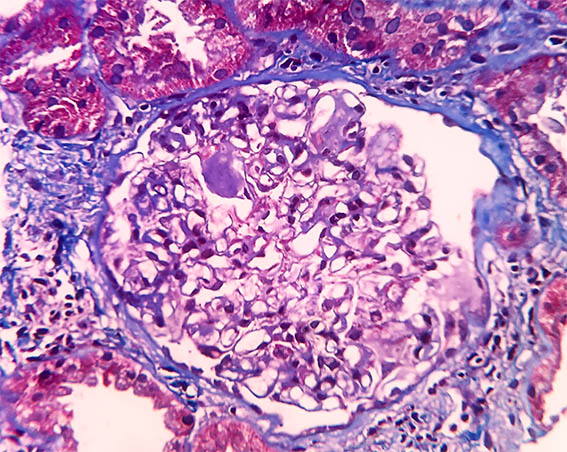

Figura 5. Tricrómico de Masson, X400.